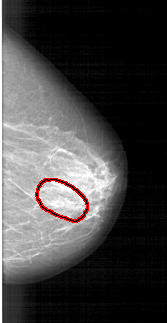

A_1390_1.LEFT_CC

RIGHT_CC LINES 5491 PIXELS_PER_LINE 2836 BITS_PER_PIXEL 12 RESOLUTION 43.5 OVERLAY

FILE: A_1390_1.RIGHT_CC.OVERLAY

TOTAL_ABNORMALITIES 1

ABNORMALITY 1

LESION_TYPE CALCIFICATION TYPE PLEOMORPHIC DISTRIBUTION LINEAR

ASSESSMENT 4

SUBTLETY 3

PATHOLOGY BENIGN

TOTAL_OUTLINES 1

BOUNDARY